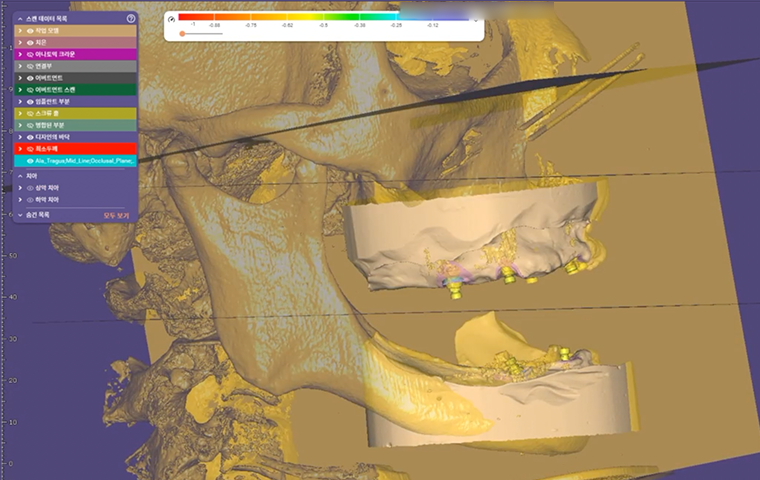

All-on-X

Practical Digital Prosthodontics: Understanding and applying

All-on-X treatment concept

Dr. Janghyun Paek

Professor at Kyunghee University, Department of Prosthodontics

All-on-X

Practical Digital Prosthodontics: Understanding and applying

All-on-X treatment concept

Dr. Janghyun Paek

Professor at Kyunghee University, Department of Prosthodontics

| 13:30 – 14:30 |

All-on-X

Dr. Janghyun Paek

|

Practical Digital Prosthodontics: Understanding and Applying All-on-X Treatment Concept |

| 13:30 – 14:30 |

All-on-X

Dr. Janghyun Paek

|

Practical Digital Prosthodontics: Understanding and Applying All-on-X Treatment Concept |

Special Pre-Day Course

Practical Digital Minimalism

Dr. Janghyun Paek

Explore the digital implant dentistry, including the All-on-X treatment concept, guide surgery, immediate loading protocols, prosthodontic considerations, and soft tissue contouring. Course also includes hands-on for All-on-X implant placement, prosthodontic components, intraoral scan, and immediate loading.

Explore the digital implant dentistry, including the All-on-X treatment concept, guide surgery, immediate loading protocols, prosthodontic considerations, and soft tissue contouring. Course also includes hands-on for All-on-X implant placement, prosthodontic components, intraoral scan, and immediate loading.